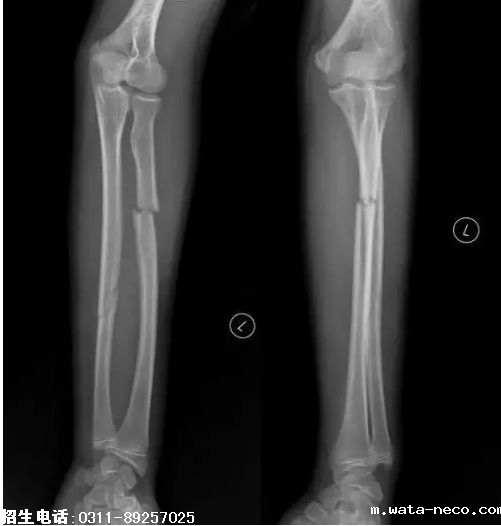

6、题干:男,15岁。左上肢外伤20分钟。结合X线片,此诊断为

A、左尺桡骨双骨折

B、左尺骨骨折

C、左桡骨骨折

D、左肱骨骨折

E、正常

答案:A

解析:由图可看出是左前臂骨折,左前臂的尺骨和桡骨均有骨折,可诊断该患者为左尺桡骨双骨折。(A对)